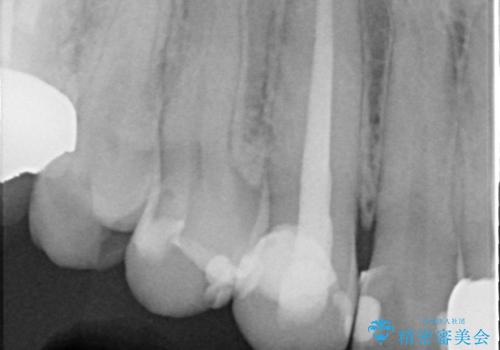

- 数年前に右上3の根管治療を行ったが、段々と色が気になってきたので、セラミックによる治療を行いたいといらっしゃった方の症例です。

再根管治療終了後、オールセラミッククラウンによる補綴を行いました。